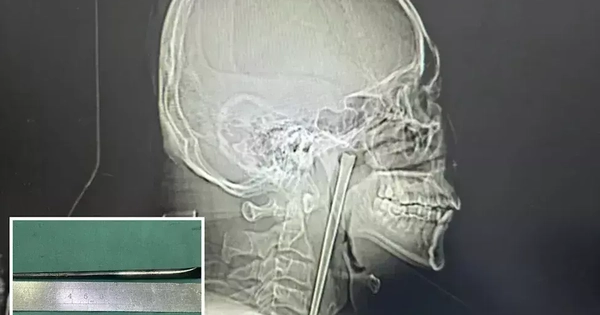

Hy hữu người đàn ông Trung Quốc sống 8 năm với chiếc đũa kim loại mắc trong cổ họng

Một trường hợp y khoa hiếm gặp vừa được ghi nhận tại Trung Quốc.